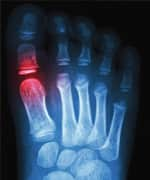

LE: Why is gout so painful?

MS: Gout is painful because needle-like crystals of uric acid are piercing joint tissues. And, as if that weren’t enough, the crystals also initiate a powerful inflammatory response that causes redness, swelling, and heat. This occurs within tight joint spaces with little ability to expand and relieve pressure.

LE: How is gout diagnosed?

MS: Classically, hyperuricemia and podagra (swollen, red big toe) are enough to make the diagnosis of gout. However, clinicians will tell you that gout doesn’t only affect the big toe. Just about any joint can be involved.

So that leaves hyperuricemia (uric acid level greater than 8.6 mg/dL in men and 7.1 mg/dL in women) and severe pain in at least one joint as the criteria for most clinicians to call it gout. But keep in mind that gout occurs without hyperuricemia, and many people with raised uric acid levels never develop gout.

In cases with normal uric acid levels, synovial fluid analysis should be considered. Although some doctors might treat for gout without one, the presence of large needle-shaped crystals within the joint fluid confirms the diagnosis and can be used to differentiate gout from pseudogout or septic arthritis.

By the way, outside of ruling out a fracture, you probably can forgo the X-ray if your doctor orders one. It won’t help in diagnosing acute gout, and should only be used to evaluate bone and joint erosions in chronic gout.